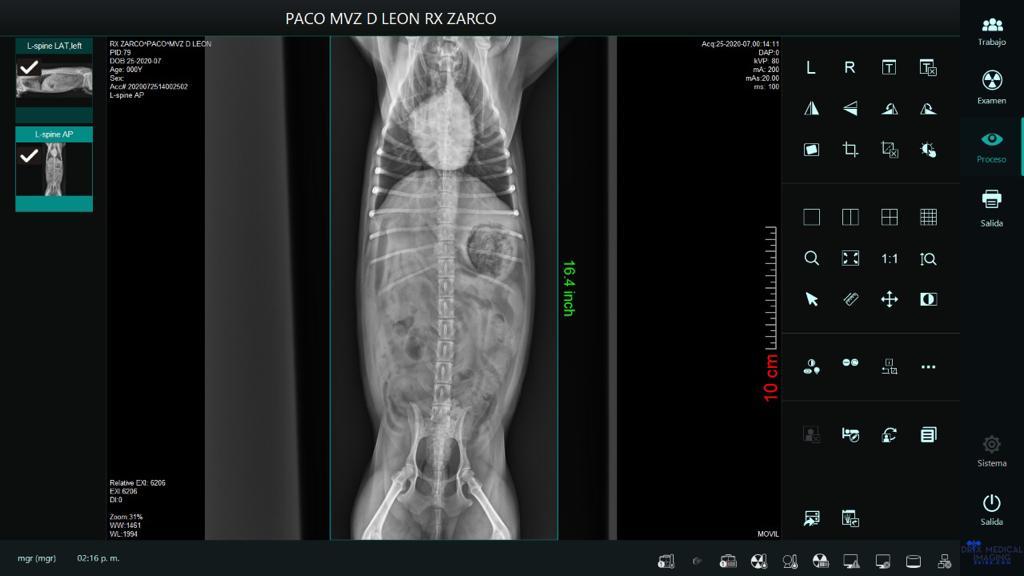

Paciente: Pako

Raza: Yorkshire

Padecimiento: Síndrome de Woobler

Paciente presentado con inicio con dolor intenso de cuello que posteriormente se convierte en una descoordinación y parálisis desde el cuello hacia sus cuatro extremidades.

En la radiografía se encuentra una compresión.